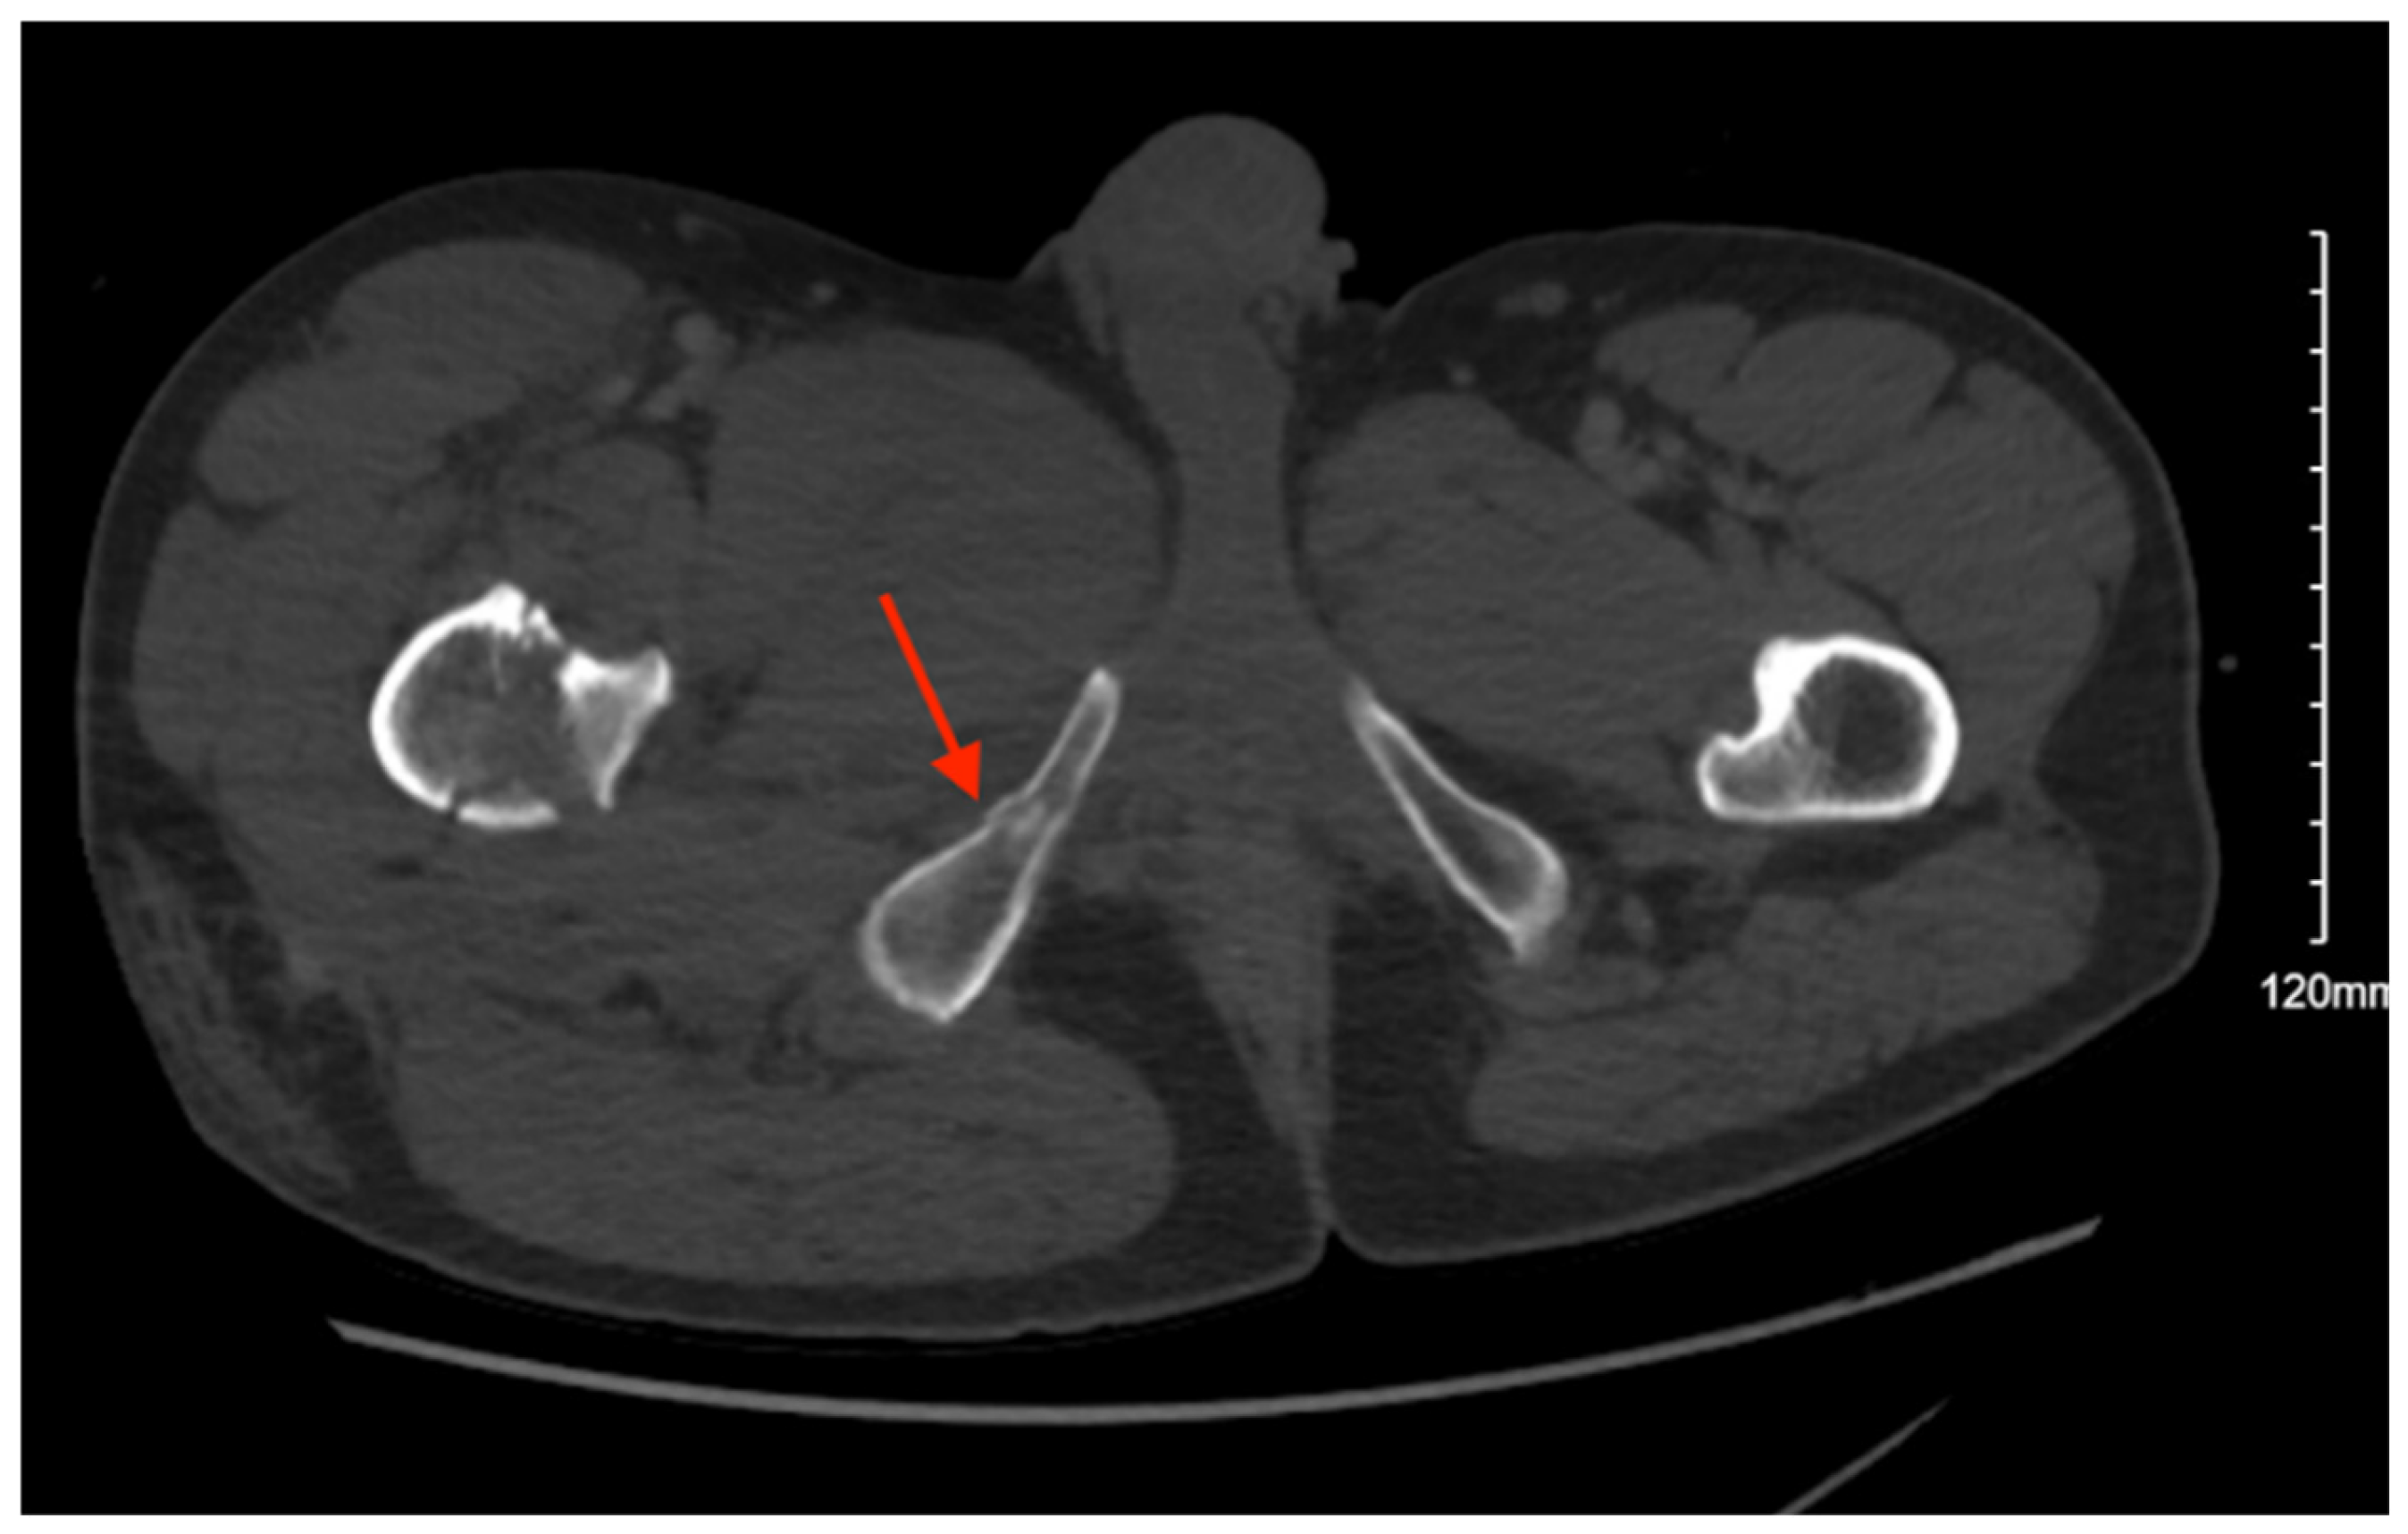

Pelvic imaging revealed acute fractures involving the right superior pubic ramus and left inferior pubic ramus, an acute comminuted avulsed fracture of the left sacral wing in the superior and midportion (Figure 1). Additional injuries included multiple facial fractures, left distal radius fracture, left femur fracture, and left tibial shaft fracture.

Figure 1. CT abdomen/pelvis images of the described fractures in case 1. Red arrows are used to indicate the location of pelvic fractures for easier identification.